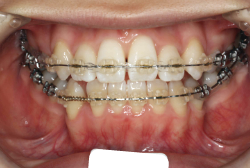

「歯並びの凸凹を直したい」という主訴で来院したケースです。診断の結果、たしかに「叢生」という隙間が足りないと言うことが原因の凸凹症例でした。

しかし、それ以上に問題なのは「前歯の噛み合い方が深すぎる」という症状で、初診の歯の正面写真を見ると下の前歯が全く見えません。こういう症状を矯正学では「過蓋咬合(かがいこうごう)」と言います。過蓋咬合を放置すると、将来的に顎関節に悪影響を与えるとされており、顎関節症の原因因子の一つです。また下の前歯の先端が、上の前歯の裏側の歯茎と強く接触するため、歯周病の原因にもなります。

検査の結果、凸凹が軽症なため非抜歯で矯正すること可能と判断、マルチブラケット装置にて治療しました。治療後は歯並びが綺麗になっただけでなく、噛み合わせ的にも正しい状態が確立しています。